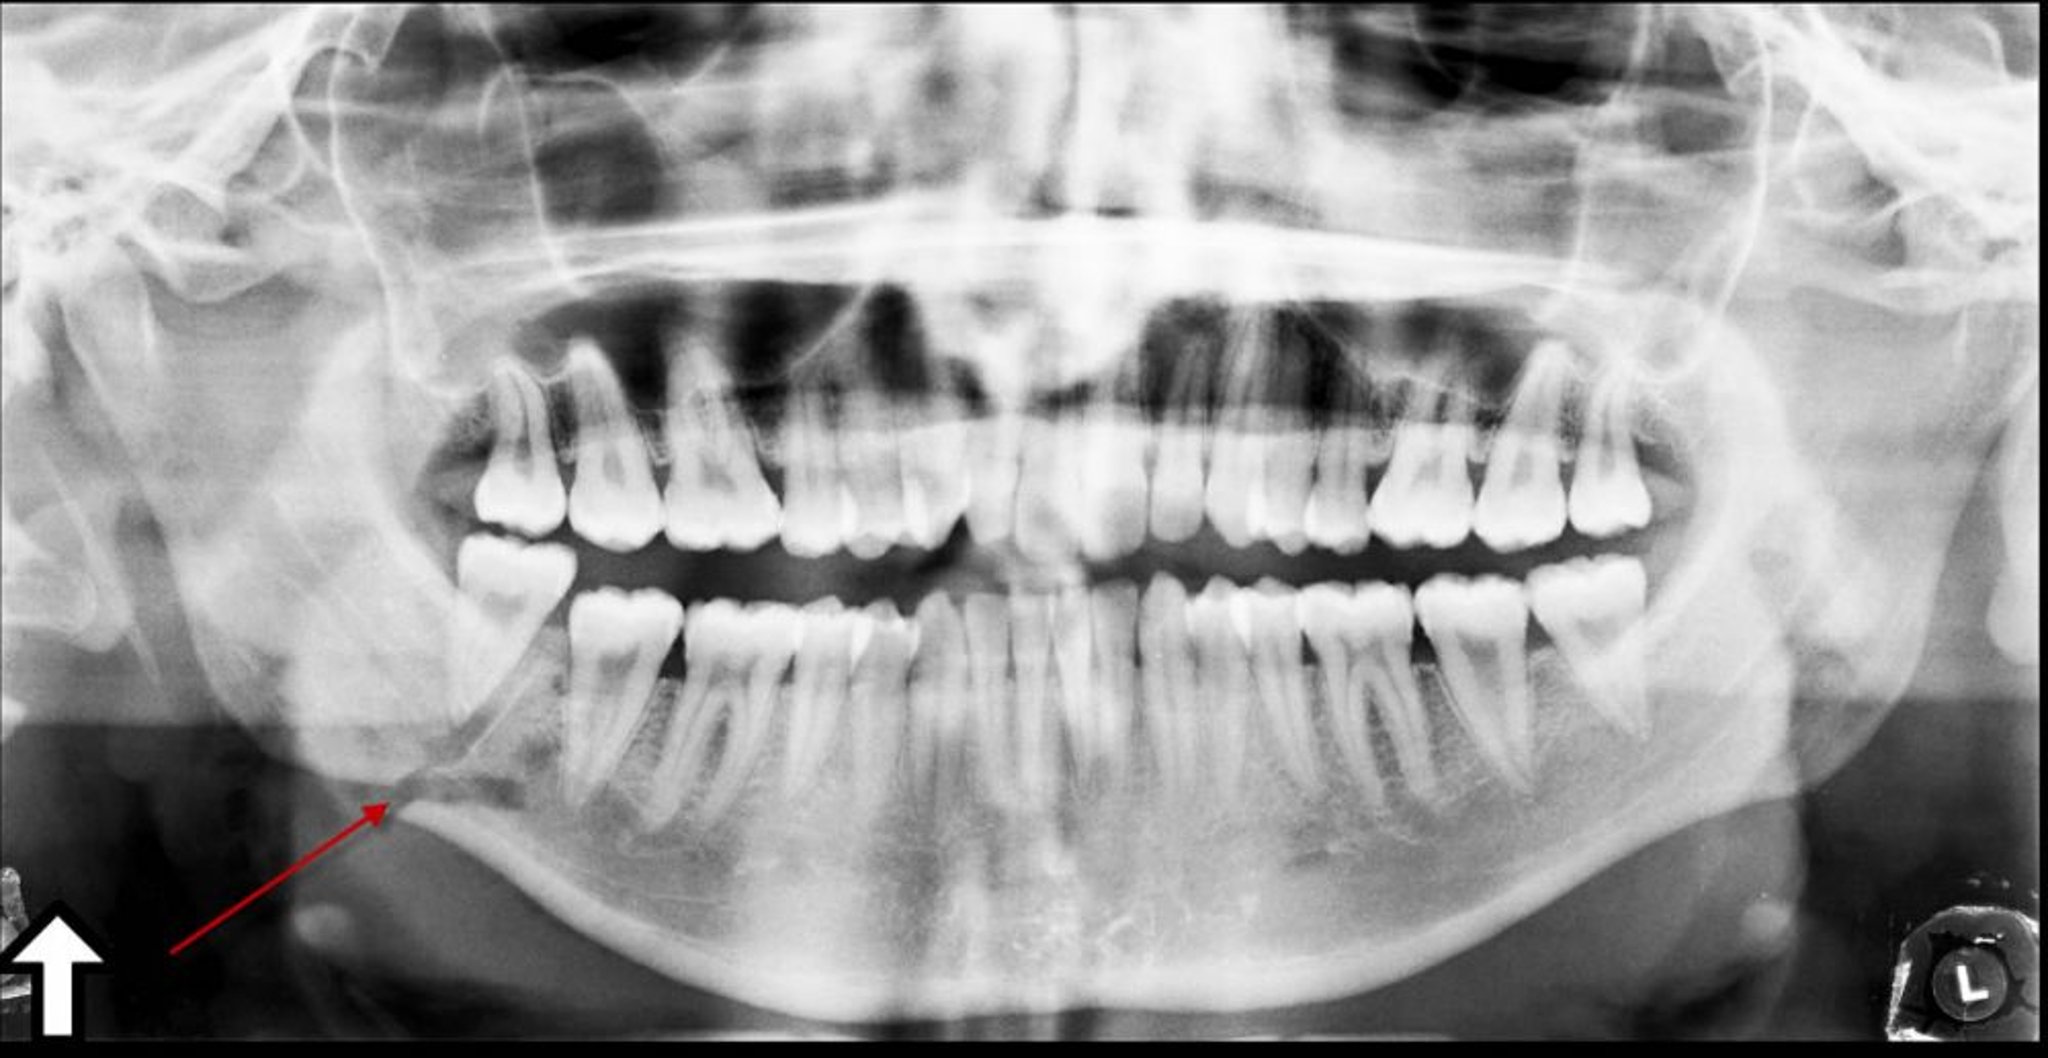

Frattura dell'angolo mandibolare

Questa radiografia panoramica mostra una trasparenza (freccia) all'angolo della mandibola, che rappresenta una frattura.